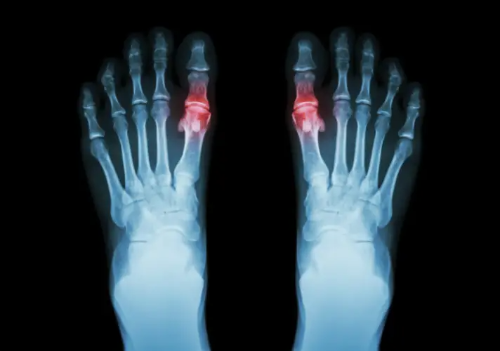

통풍은 요산이 체내에 과다하게 축적되어 생기는 질환입니다. 요산은 인체에서 생성되는 노폐물로, 신장을 통해 배출됩니다. 그러나 신장의 기능이 떨어지거나, 요산이 과다하게 생성되면 체내에 축적됩니다. 요산이 관절의 연골, 힘줄, 주위조직에 날카로운 형태의 결정으로 침착되면 조직들의 염증반응을 촉발시켜 심각한 통증을 유발합니다.

가장 일반적인 증상으로, 갑작스럽고 극심한 통증이 발생합니다. 주로 발의 큰 발가락 관절에서 시작하여 다른 관절로 확산될 수 있습니다.

피부에 붉은 반점이 생길 수 있습니다. 주로 통증이 있는 부위에서 발생하며, 염증 반응으로 인한 현상입니다.